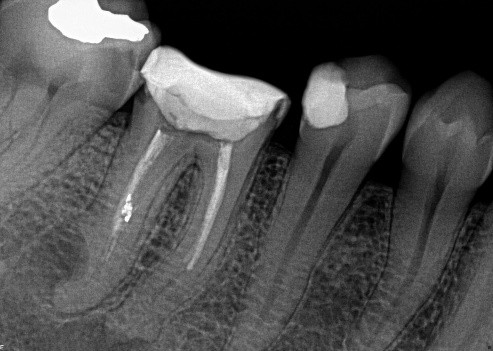

8. Select ONE OR MORE correct answers)

Which of the following may complicate the extraction of tooth 1.6?

10. (Select ONE OR MORE correct answers.)

Which of the following may complicate the extraction of tooth 3.6?

20. (Select ONE OR MORE correct answers.)

Which of the following may complicate the surgical extraction of tooth 1.6?

21. (Select ONE OR MORE correct answers.)

Which of the following may complicate the extraction of tooth 4.6?

22. (Select ONE OR MORE correct answers.)

Tooth 1.6 is planned for extraction. Which are the most likely postoperative complications?